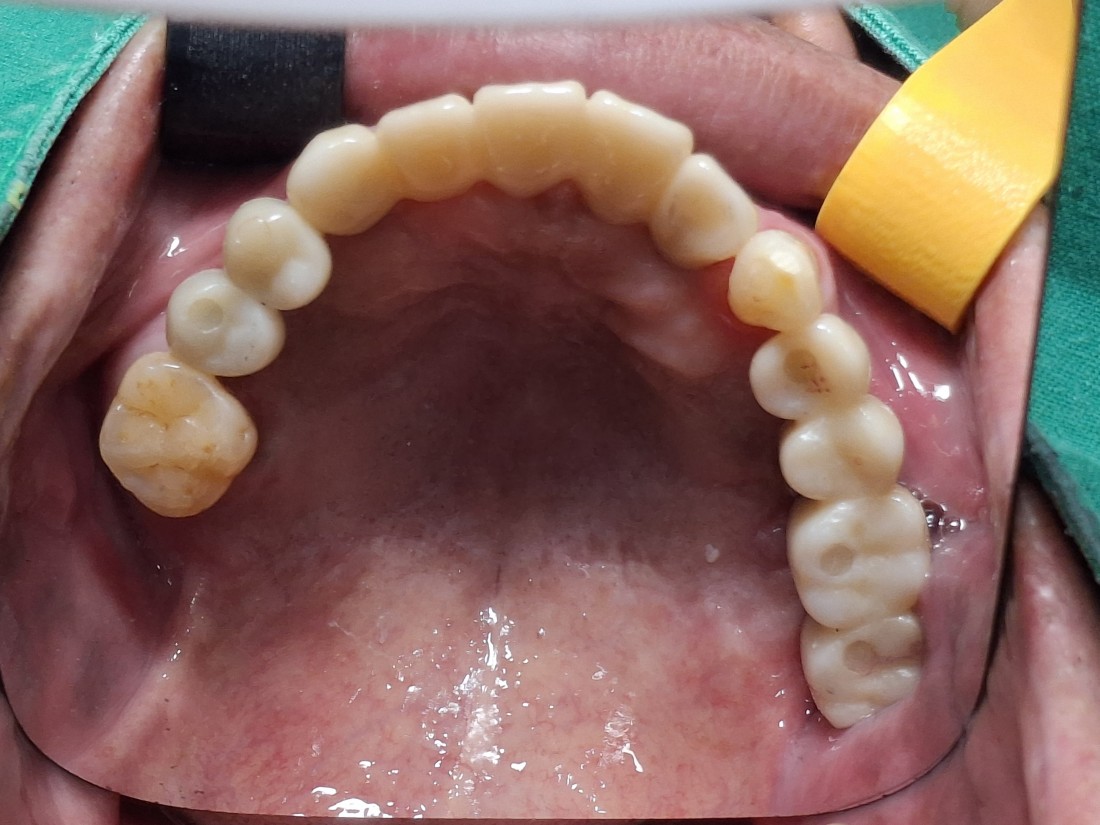

한 번에 8개 이상 식립이 가능한

광주 앞니 임플란트 치과의

디지털 가이드 임플란트로

아프지 않은 임플란트!

디지털 가이드 임플란트는

잇몸을 무절개 (최소절개)로 하여

임플란트 식립이 가능합니다.

그렇기 때문에 수술시간이 짧으며,

붓기 / 출혈 / 통증이 적어서

회복도 매우 빠르다는 큰 장점이 있습니다.

광주 앞니 임플란트치과의

아프지 않은 / 예쁜 / 잘 씹어지는

앞니 임플란트로

새로운 미소를 되찾아보세요!